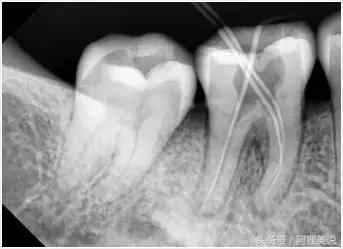

3、确定根管工作长度

应用平行投照X线方法、根管长度测量仪确定根管度,最好插针拍X片。

6、根管充填

封闭整个根管系统、堵塞主根管和侧副根管出口、防止微生物和液体的渗漏。无论是侧方加压法还是垂直加压法,应做到根管充填致密,根管充填后X线片上无根管腔隙,也不能超出根尖孔。

X片:牙周膜间隙正常或轻度增厚,原有根尖病变缩小或消失;根尖未发育完全者,术后3—6个月逐渐形成;根管三维充填,根充物距根尖0.5—2.0mm。